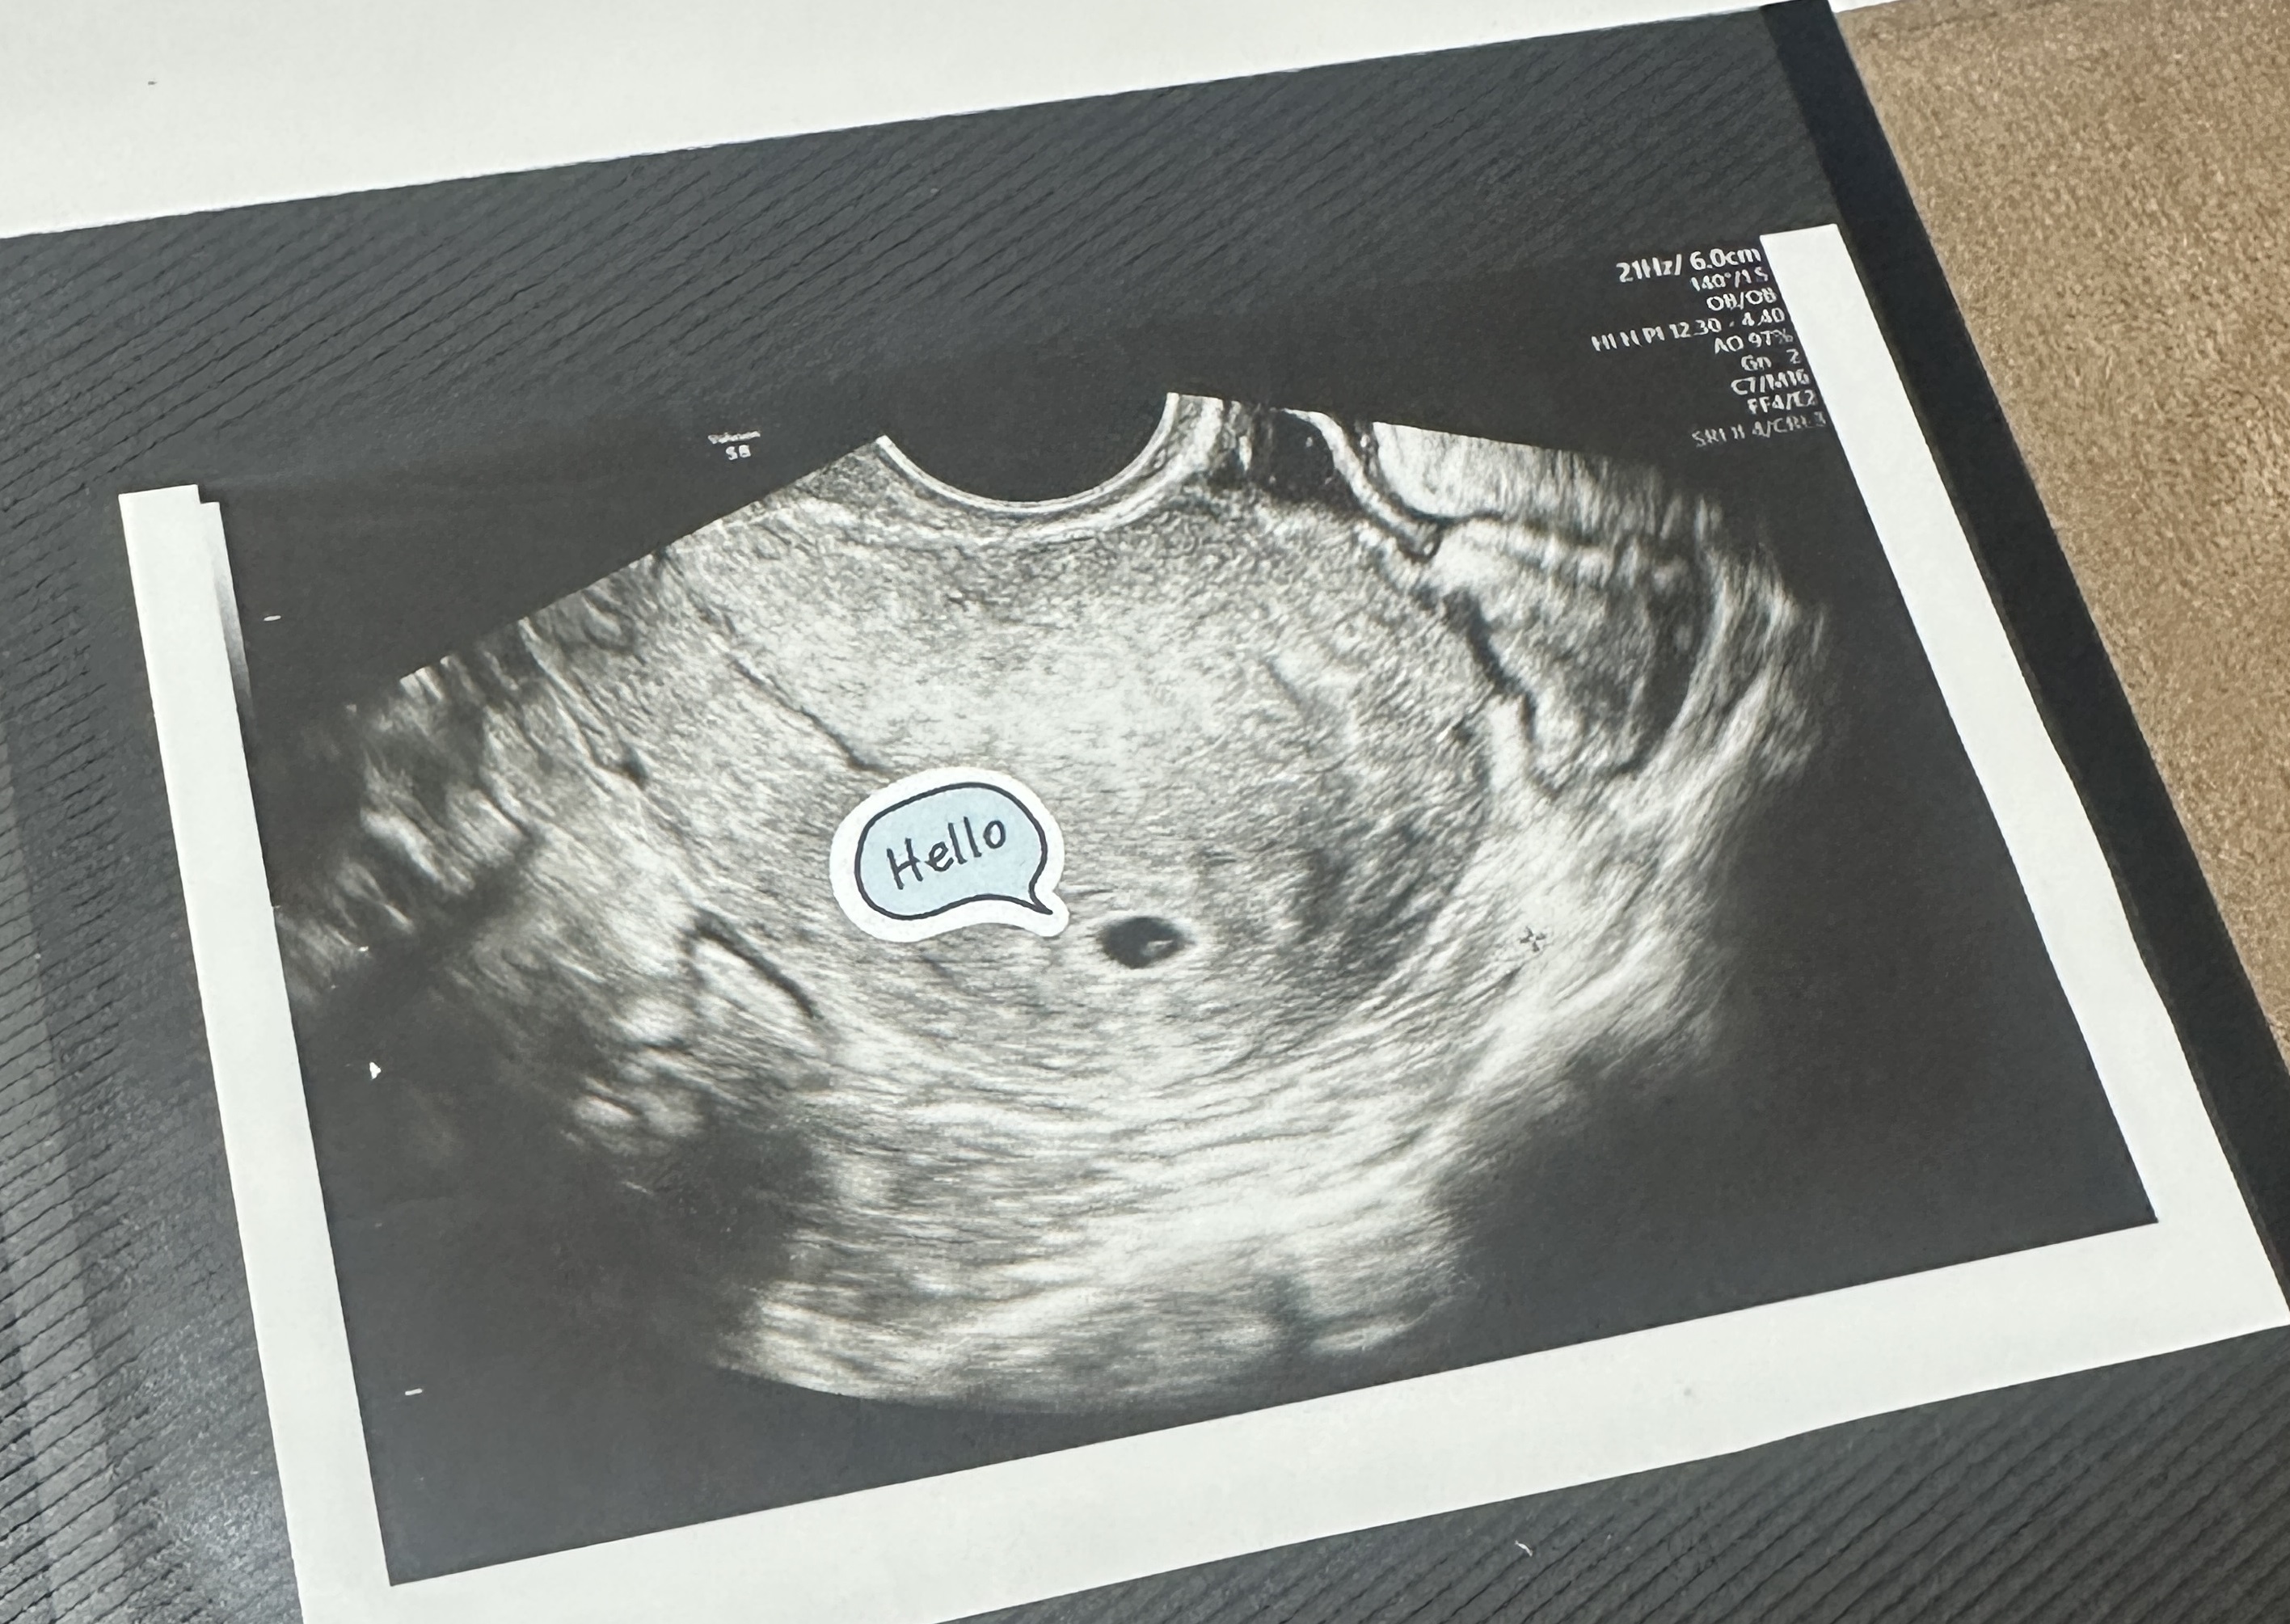

| 가슴 떨리는 임신 이야기를 공유해 주세요. | 동결 1·2차에서 실패하며 크게 흔들렸습니다. 그래도 끝까지 포기하지 않고 진행한 동결 3차에서 드디어 아기집이 확인되었을 때, 너무 놀랍고 벅차서 눈물이 날 만큼 기뻤습니다. 그 순간만큼은 지금도 잊히지 않습니다. |

| 치료 도중 느꼈던 가장 기뻤던 순간과 절망적인 것들은 무엇인가요? 잊지 못할 경험이 있나요? | 가장 기뻤던 순간은 역시 동결 3차에서 아기집이 확인된 날이었습니다. 반대로 가장 절망적이었던 때는 1·2차 이식이 실패했을 때였습니다. 기대했던 만큼 마음이 무너져 내렸었어요. |